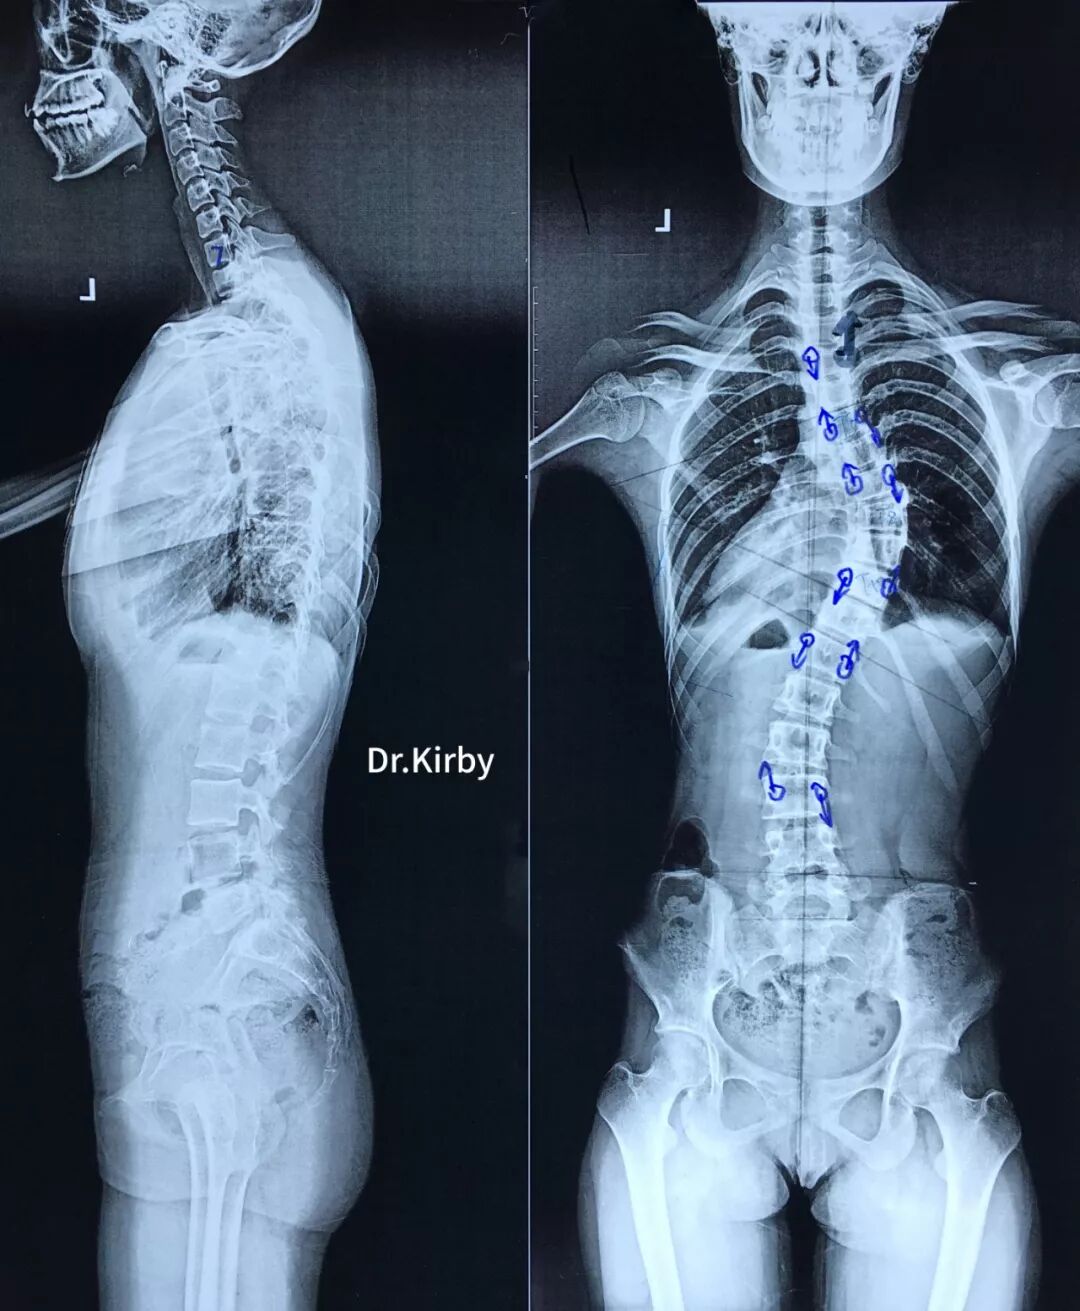

16歲的小蓉家在云南,10個(gè)月之前診斷出患有“脊柱側(cè)彎”。幾經(jīng)輾轉(zhuǎn),經(jīng)人介紹,小蓉來到了省級知名骨科專家、邦爾骨科集團(tuán)首席專家、嘉興邦爾骨科醫(yī)院院長趙凱教授的專家門診。

經(jīng)過檢查,小蓉的脊柱側(cè)彎屬于“青少年特發(fā)性脊柱側(cè)彎”, 隨著年齡的增長和身高的發(fā)育,小蓉的脊柱側(cè)彎度會(huì)不斷擴(kuò)大,及時(shí)進(jìn)行手術(shù)治療十分必要。

趙凱教授帶領(lǐng)脊柱外科團(tuán)隊(duì)為小蓉進(jìn)行了“脊柱側(cè)彎后路矯形術(shù)”,術(shù)后在脊柱外科副主任朱科林醫(yī)生和康復(fù)醫(yī)師共同的努力下,小蓉側(cè)彎的脊柱得到了良好的矯正,手術(shù)效果立竿見影。

術(shù)前術(shù)后對比圖

術(shù)前X線片

術(shù)后X線片